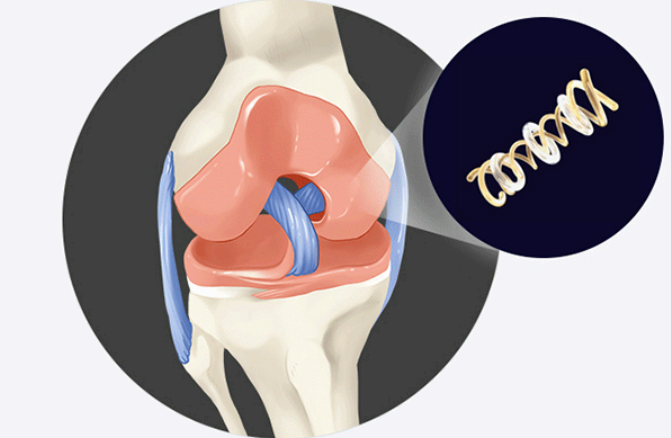

콘드로이친은 그리스어로 관절이라는 뜻이며 콘드로이친은 관절과 연골을 구성하는 주요 성분 중 하나입니다. 관절과 연골의 구성 주요 성분은 콘드로이친, 글루코사민이 대표적인데 이러한 콘드로이친은 나이가 들 수록 점점 감소하여 꾸준히 콘드로이친 섭취하여 관절 건강을 챙겨주어야 합니다.

노화가 진행되면서 연골의 노화와 손상으로 염증과 통증이 발생되게 되는데 이러한 연골의 1/3을 차지하는 핵심성분이 콘드라이친이라고 생각하시면 편리합니다.

위에 사진 중 노란색으로 되어있는 연골과 연골 사이의 매트릭스 구조의 역할을 하는 연골 탄성섬유의 주성분이 콘드로이친으로 관절 윤활제로써 연골의 마모를 감소시키며 연골 세포 생존에 필요한 영양공급을 성분입니다.

콘드로이친 1200은 사람 연골과 구조가 동일한 소 연골의 콘드로이친만을 사용하여 관절 건강에 도움이 될 가능성이 높고 순도 90% 이상으로 정제된 콘드로이친 황산 원료를 이용하는 것으로 유명합니다.